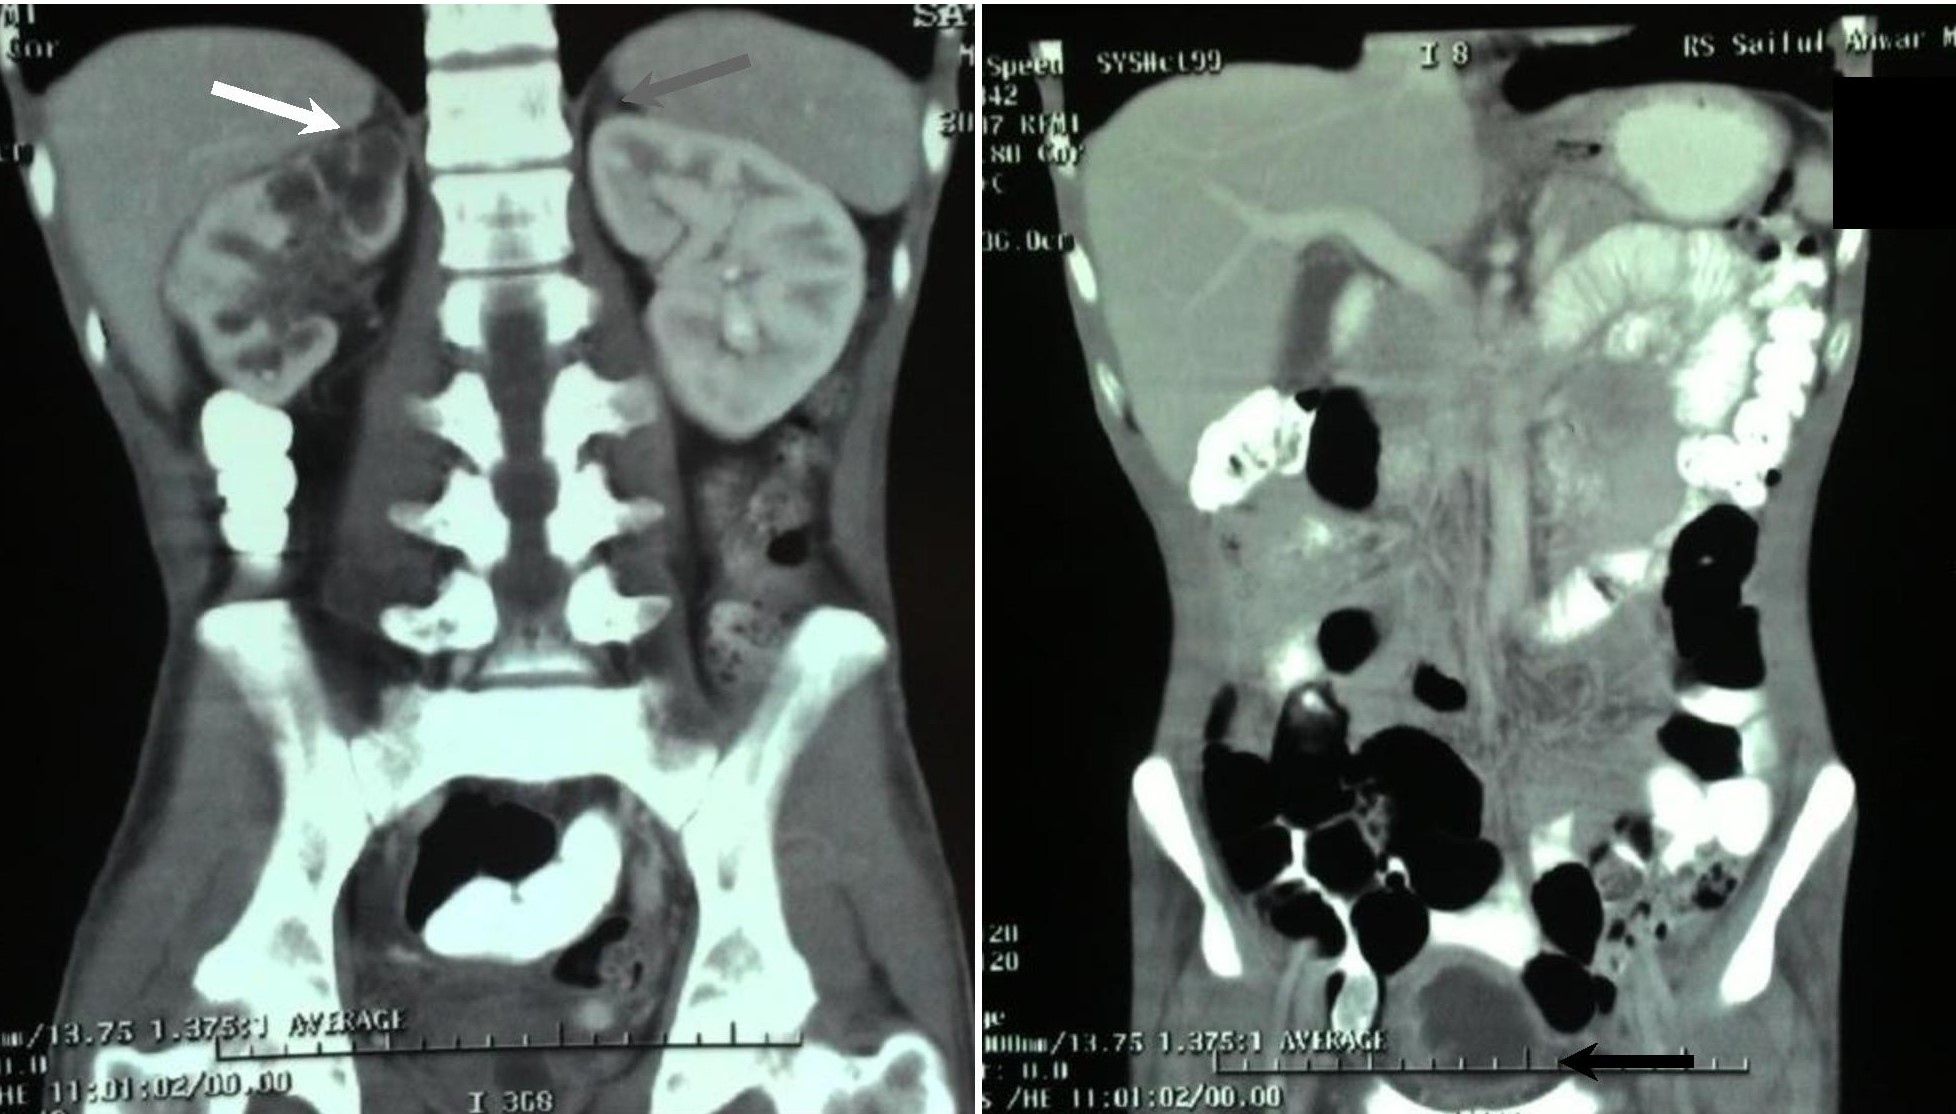

Ultrasonography of the neck revealed left perijugular lymphadenopathy. Plain chest and apicolordotic radiographs revealed moderate pulmonary TB (Figure 2). Urinalysis revealed albuminuria, pyuria, hematuria and bacteriuria (Table 1). Staining for acid-fast bacilli (AFB) was negative in sputum samples, and positive (+) for urine specimen. Urine culture showed no bacterial growth. Abdominal ultrasound revealed bilateral grade II to III hydronephrosis and chronic cystitis. This was consistent with subsequent findings in the intravenous urogram, which showed bilateral grade III hydroureteronephrosis due to obstruction at the distal ureters and contracted urinary bladder. However, histopathology result of urine cytology showed non specific chronic inflammation. Computerized tomography (CT) of the abdomen showed left adrenal gland hypoplasia, multiple cysts on the right adrenal gland, grade III to IV right hydronephrosis, grade II left hydronephrosis, chronic ureteritis and cystitis (Figure 3).

Figure 3. CT scan of the abdomen on coronal view showed a right adrenal gland measuring 3.3 cm x 2.6 cm with multiple cysts (white arrow), a hypoplastic left adrenal gland measuring 1.4 cm x 0.9 cm (normal value 4 cm x 2 cm) (gray arrow), right hydronephrosis grade III to IV, left hydronephrosis grade II, chronic ureterithis and cystitis (black arrow).

TB of the adrenal glands may be seen on CT scan imaging as bilateral enlargement on active infection, followed by atrophy and calcification on remote infection. We think our patient had remote infection in both adrenal glands, despite the absence of calcification. Calcification is observed in longstanding TB infection, with incidence on CT imaging varying from 40 to 59%. Adrenal cysts have been reported to be caused by Echinococcus species. However, since Echinococcus infection is rare in Indonesia, and the patient’s clinical appearance and fecal analysis did not support the evidence of infection, we concluded that TB was the main cause of adrenal insufficiency in our patient.3,12,16-18